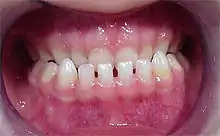

Un diastème (ou diastématie) (du grec διάστημα / diástêma, « intervalle ») est, en odontologie, un écartement entre deux dents normalement adjacentes. Il est plus fréquemment rencontré entre les deux incisives centrales de la mâchoire supérieure. Il peut être congénital ou acquis.

Le diastème entre les incisives supérieures (diastème interincisif) est dû à la présence d'un frein labial (tendon qui attache les lèvres à la mâchoire) trop puissant et qui ne se rétracte pas suffisamment lorsque les dents poussent[1]. Il peut-être dû aussi à une pulsion de la langue lors de la déglutition et/ou de l'articulation.